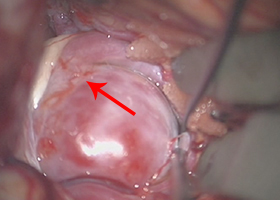

①くも膜下出血の原因となる脳動脈瘤(のうどうみゃくりゅう)の外科治療

63歳女性、左眼視力低下で発症

[画像所見]

-

右 MRI画像 -

CT画像 左 -

脳血管撮影画像

左眼の奥に大きな動脈瘤認めます。 -

造影三次元CT画像

[手術方法]

左前頭側頭開頭で動脈瘤クリッピング術を行った。手術中は脳血管撮影装置を用いたHybrid手術を施行し、動脈瘤の消失を手術中に確認する。

Hybrid手術 -

手術中MEP(運動神経)VEP(視力)モニタリングで術後の視力低下や手足の麻痺を予防します。

実際の手術所見

動脈瘤(赤矢印) -

クリップ留置(瘤の消失:赤矢印)

手術中の脳血管撮影画像

(手術前) -

クリップ留置後、瘤(こぶ)は消失 -

(手術後) -

術後CT -

患者様は術前からあった左視力低下以外に神経症状なし。元気に自宅退院されました。